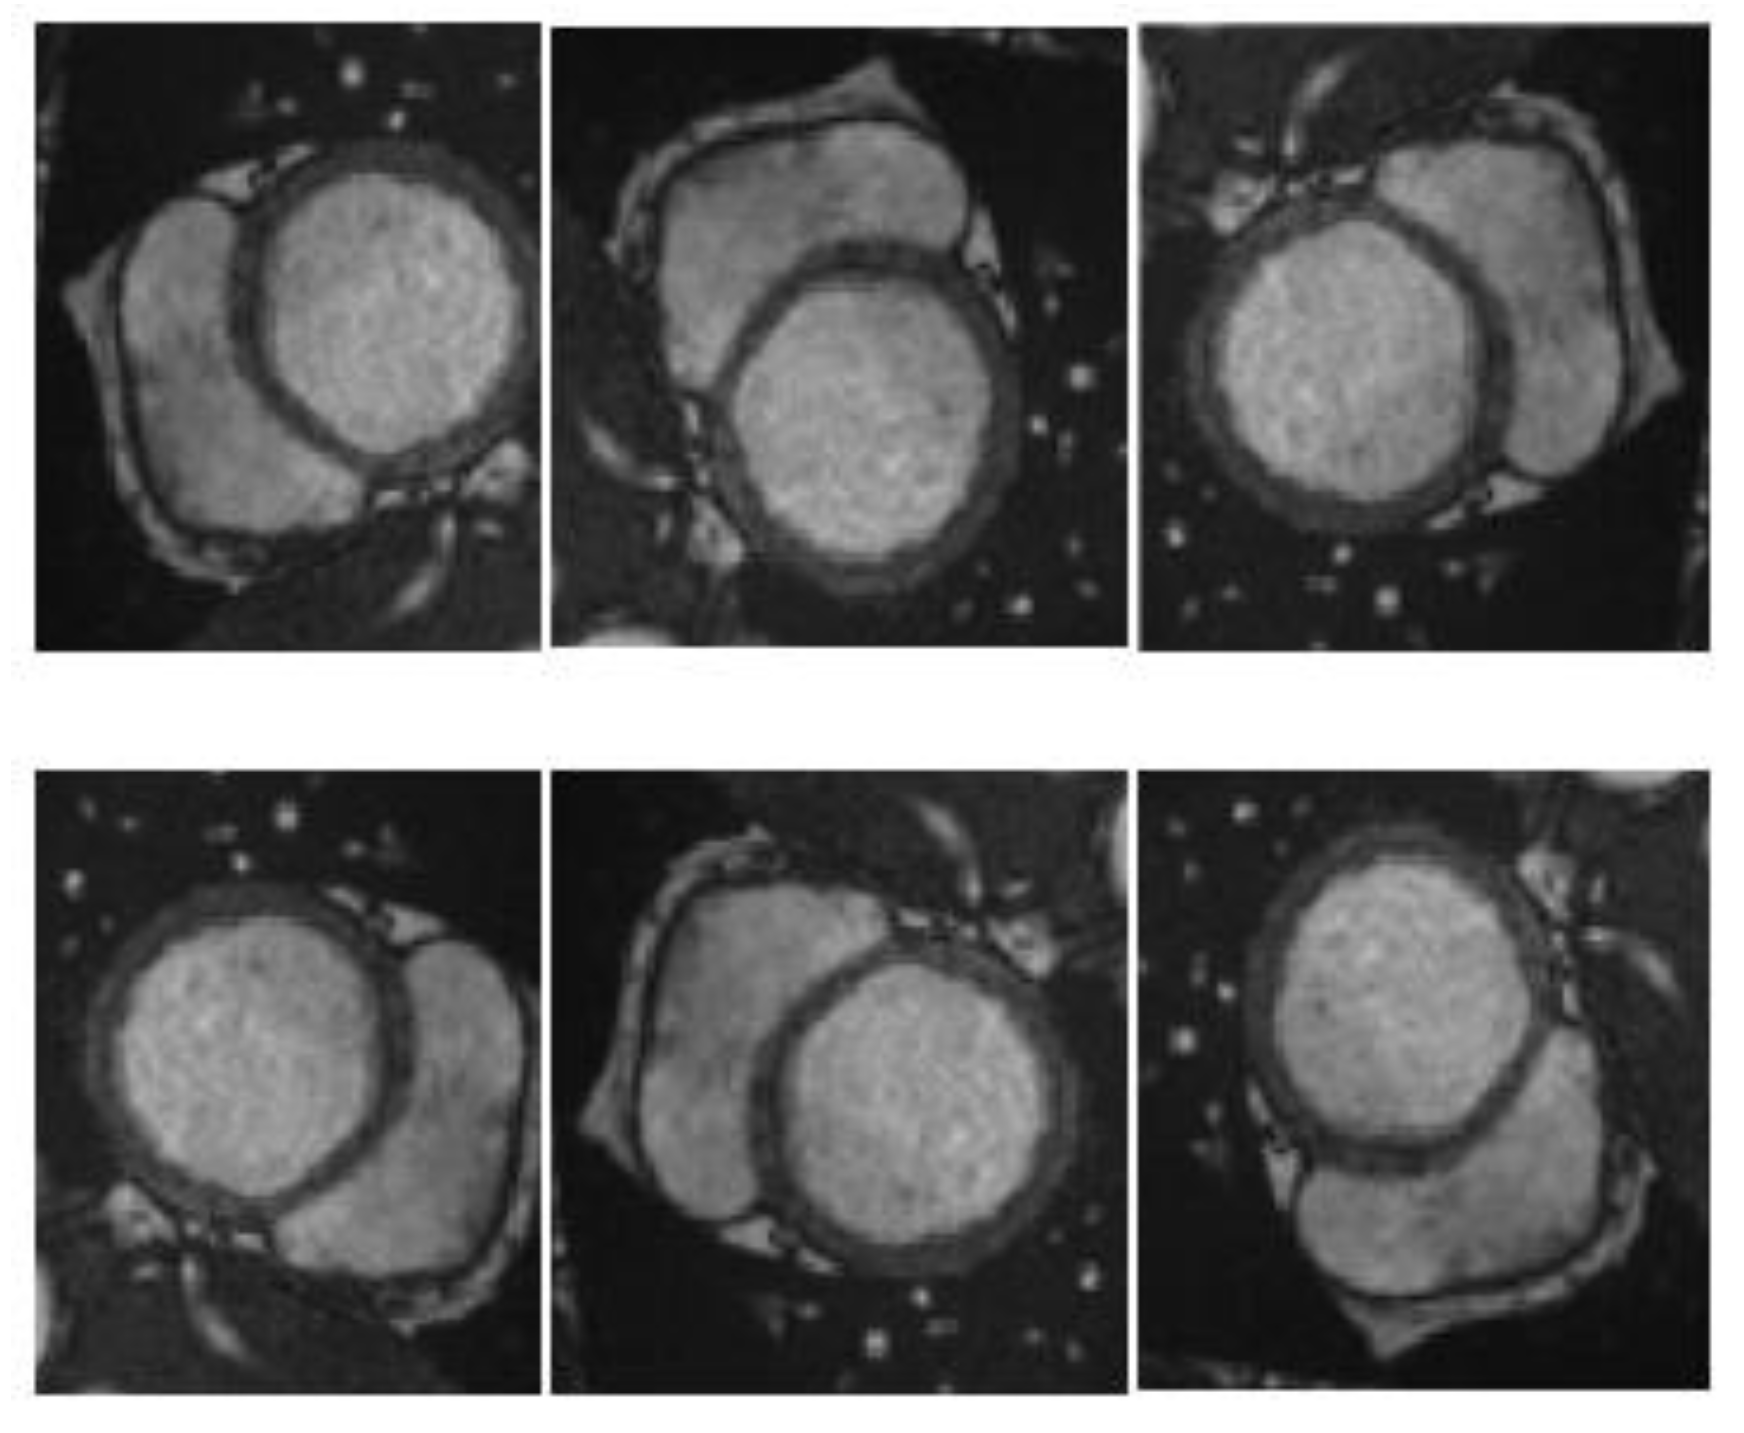

The training effectiveness of the datasets plays a significant role in the final performance of the network. Training neural networks generally requires a massive amount of data to achieve the desired results; however, for medical images, the amount of data manually annotated by experts is very small. Inadequate data can cause overfitting. Overfitting leads to excellent performance on the training set, but unsatisfactory performance on the testing set. Therefore, the data were enhanced via techniques, including rotation and mirroring, to expand the data volume and prevent overfitting as shown in Figure 4.

Figure 4. Schematic diagram of data enhancement.